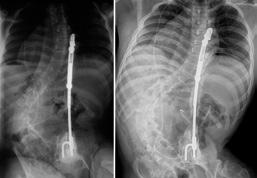

Implantes para la estabilización vertebral diseñados y aplicados en la Clínica de Columna. (Izq.) Rectángulo modelado con dispositivo de cierre “Codo de Dufoo”, (Centro) Sistema “SD” de instrumentación vertebral, (Der.) Implante para estabilización in situ de listesis lumbar L5/S1.

Sistema “SD” de instrumentación vertebral

Durante el periodo de estabilización vertebral con el uso de tornillos transpediculares, se presentaron dificultades con los tornillos de base fija, lo que obligaba a la recolocación frecuente del tornillo por no estar alineado con la barra. Con la aparición de los tornillos con base móvil, este problema se volvió menos frecuente. Sin embargo, consideramos que “el raquis del paciente debe ajustarse al perfil del implante”. Este criterio fue discutido con diferentes asesores de los centros de investigación mencionados previamente.

Por ello, diseñamos un sistema de barras sujetas con tornillos transpediculares, permitiendo que el ensamble sea ajustable al ángulo de colocación del tornillo transpedicular, a la curvatura vertebral, a la distancia interpedicular y a la distancia entre segmentos vertebrales. Con esta flexibilidad de orientación en los ensambles, logramos que el sistema de estabilización “SD” se adapte a la anatomía vertebral del paciente sin modificar la resistencia de la instrumentación ni forzar los ensambles. Resultados publicados.